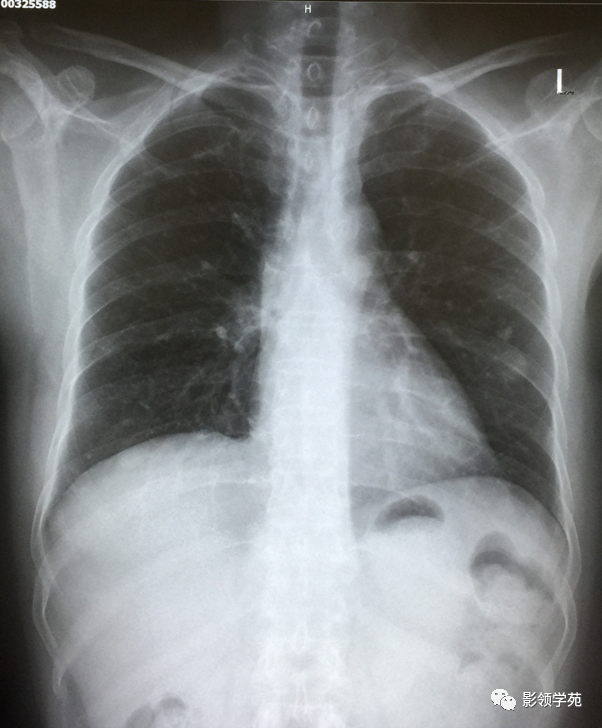

瘤外科患者,女,48,左乳癌根治术后2月术后化疗。病理:左乳伴髓样癌特征的乳腺浸润性导管癌。术后TAC方案化疗1个周期。

左乳切除术后,左肺下野两个大小不等高密度影。